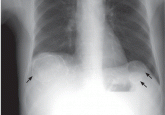

ArticleCalcified cysts in the upper abdomenAuthor:Hung-Chun Chen, MD, PhDPublish date: February 1, 2010A plain chest radiograph reveals multiple calcified cysts in the upper abdomen of a man who has been on dialysis for 15 years. What is the most pla...Read More